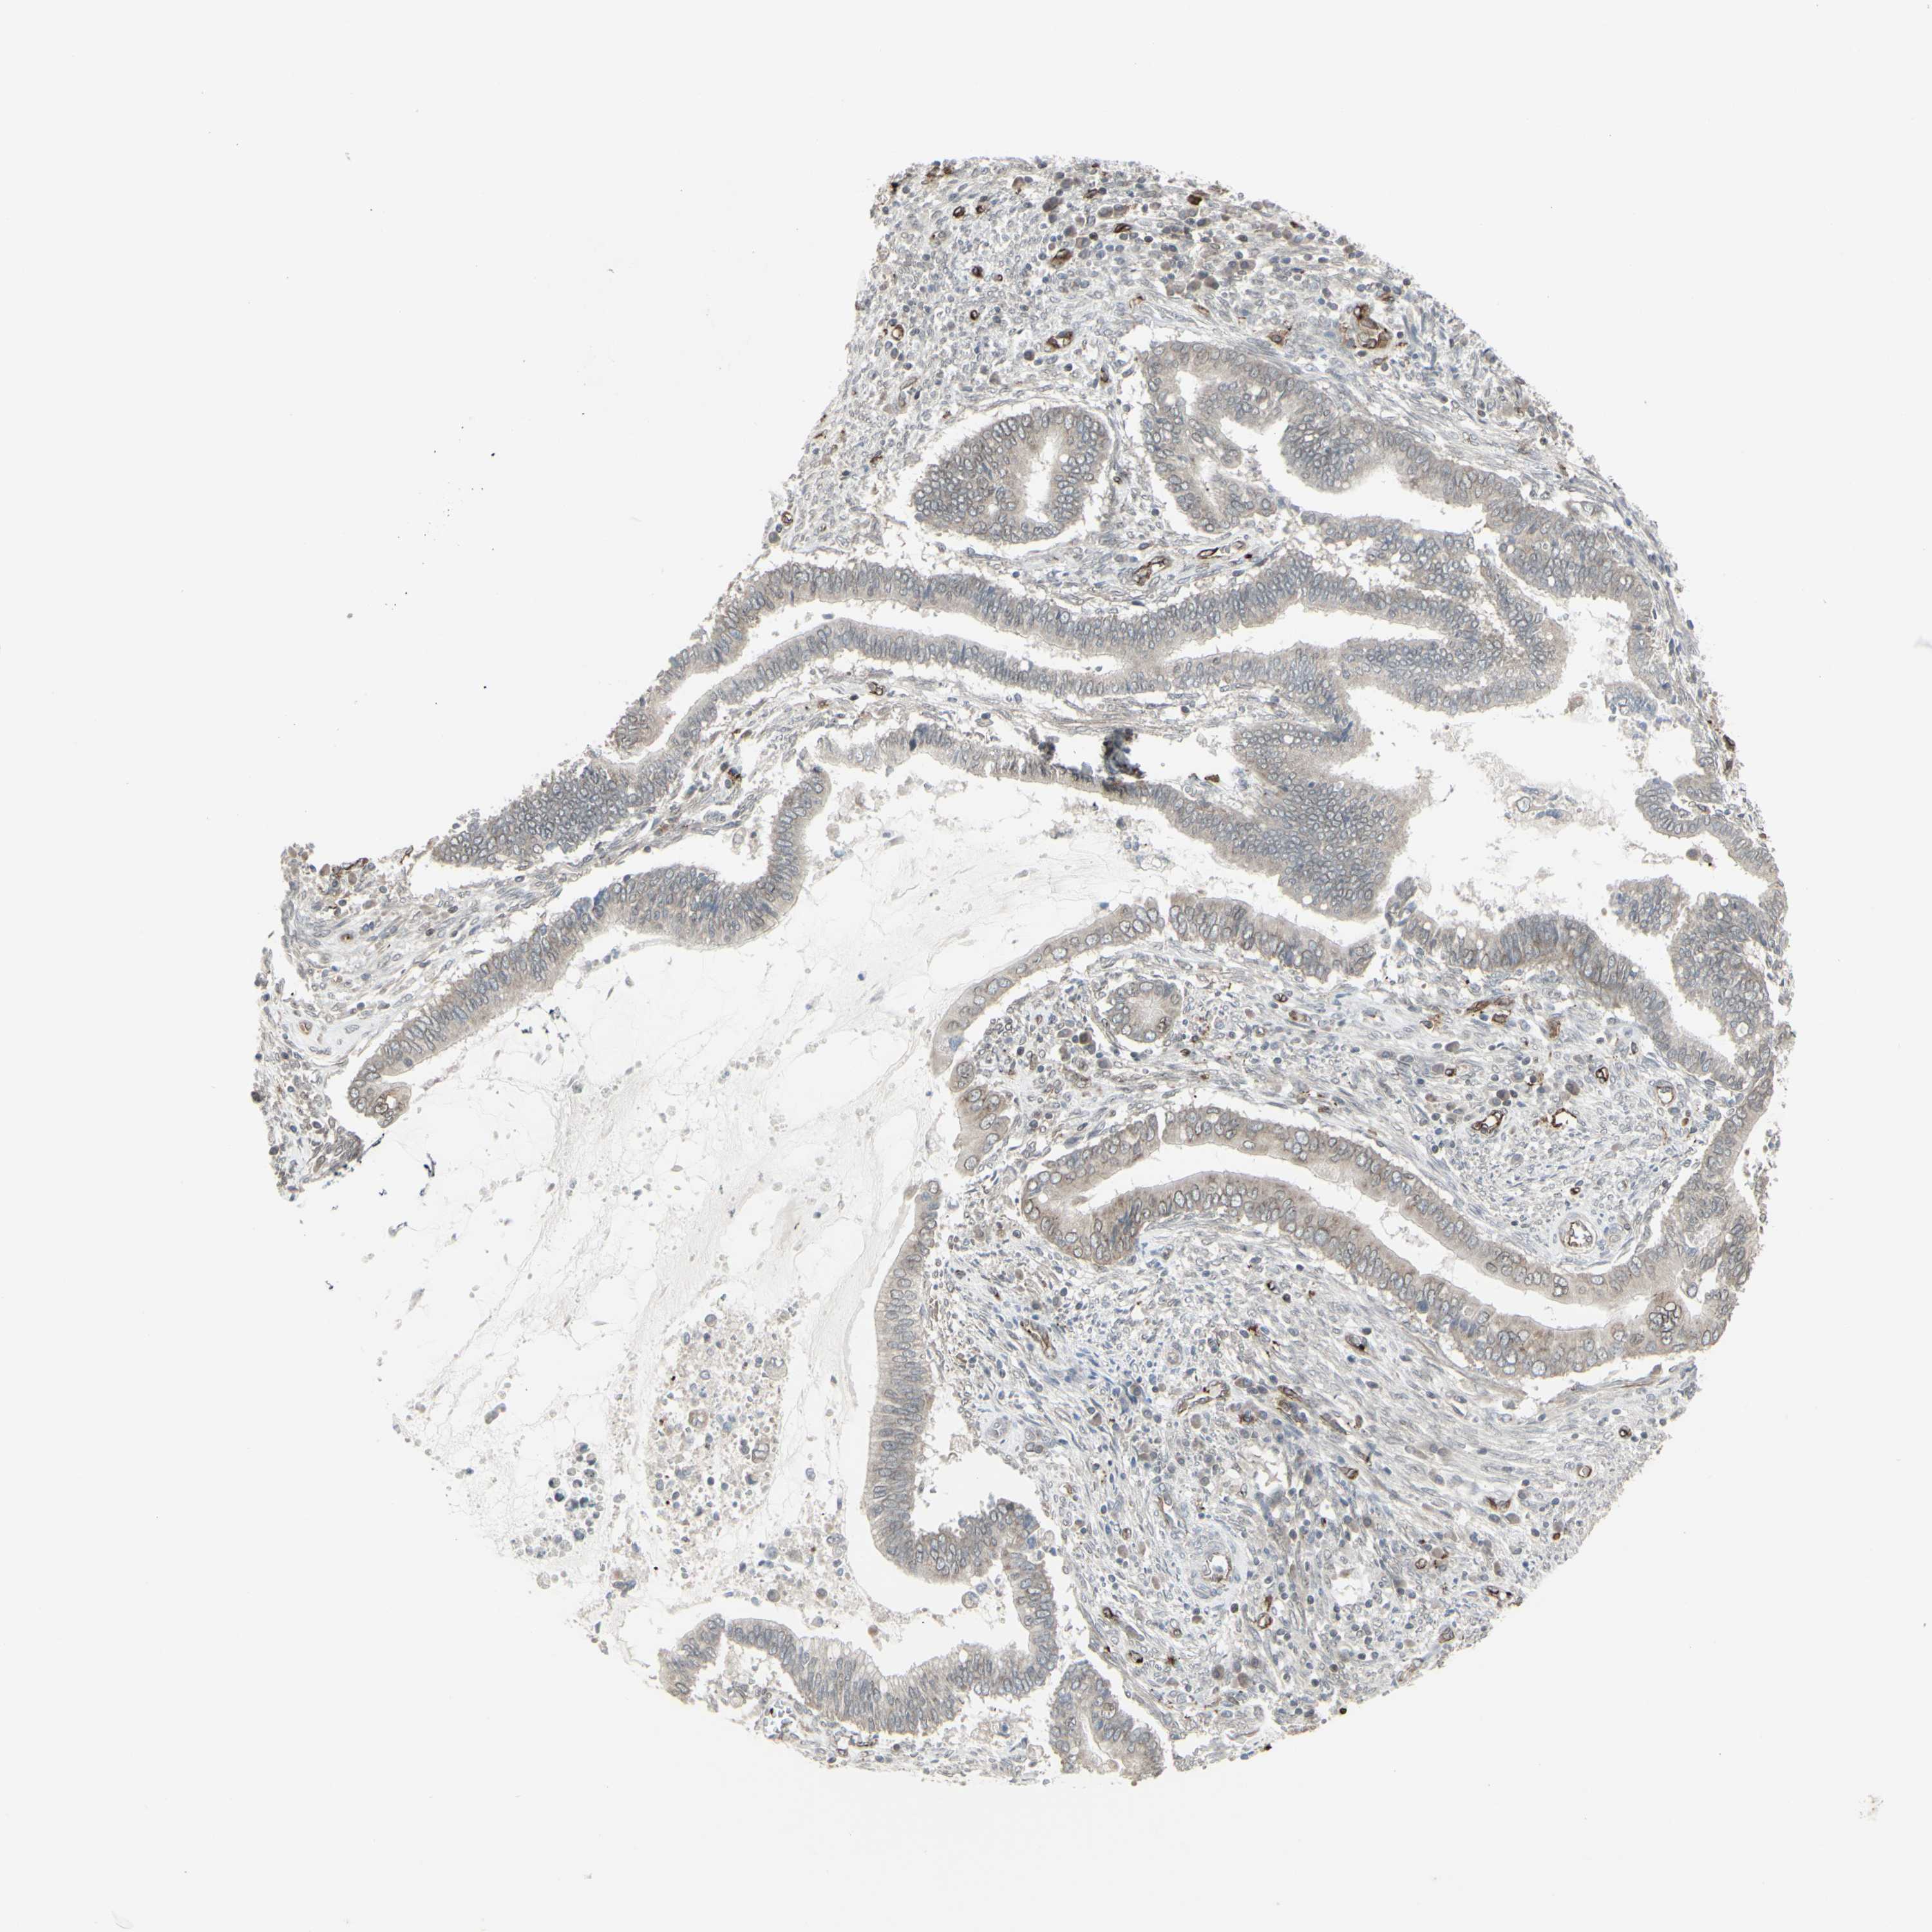

CERVICAL CANCER - Protein expressioni

A mouse-over function shows sample information and annotation data. Click on an image to view it in a full screen mode. Samples can be filtered based on level of antibody staining by selecting one or several of the following categories: high, medium, low and not detected. The assay and annotation is described here.

Note that samples used for immunohistochemistry by the Human Protein Atlas do not correspond to samples in the TCGA dataset.

Antibody stainingi

Antibody staining in the annotated cell types in the current human tissue is reported as not detected, low, medium, or high, based on conventional immunohistochemistry profiling in selected tissues. This score is based on the combination of the staining intensity and fraction of stained cells.

Each image is clickable and will lead to virtual microscopy that enables deeper exploration of all samples and also displays staining intensity scores, fraction scores and subcellular localization as well as patient and tissue information for each sample.

Antibody HPA010570

Staining

High

Medium

Low

Not detected

Intensity

Strong

Moderate

Weak

Negative

Quantity

>75%

75%-25%

<25%

None

Location

Nuclear

Cytoplasmic/membranous

Cytoplasmic/membranous,nuclear

Adenocarcinoma, NOS